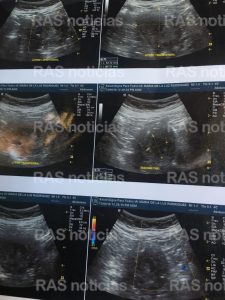

Ella pensaba que sería uno solo, pues ahí se vería que era lo que tenía. Solo que los encargados no podían dar crédito al resultado de la imagen y le hicieron ocho placas más, para que no quedada ninguna duda.